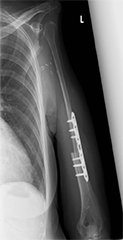

上腕骨腫瘍に対し、広範切除術と腓骨移植術を行った。